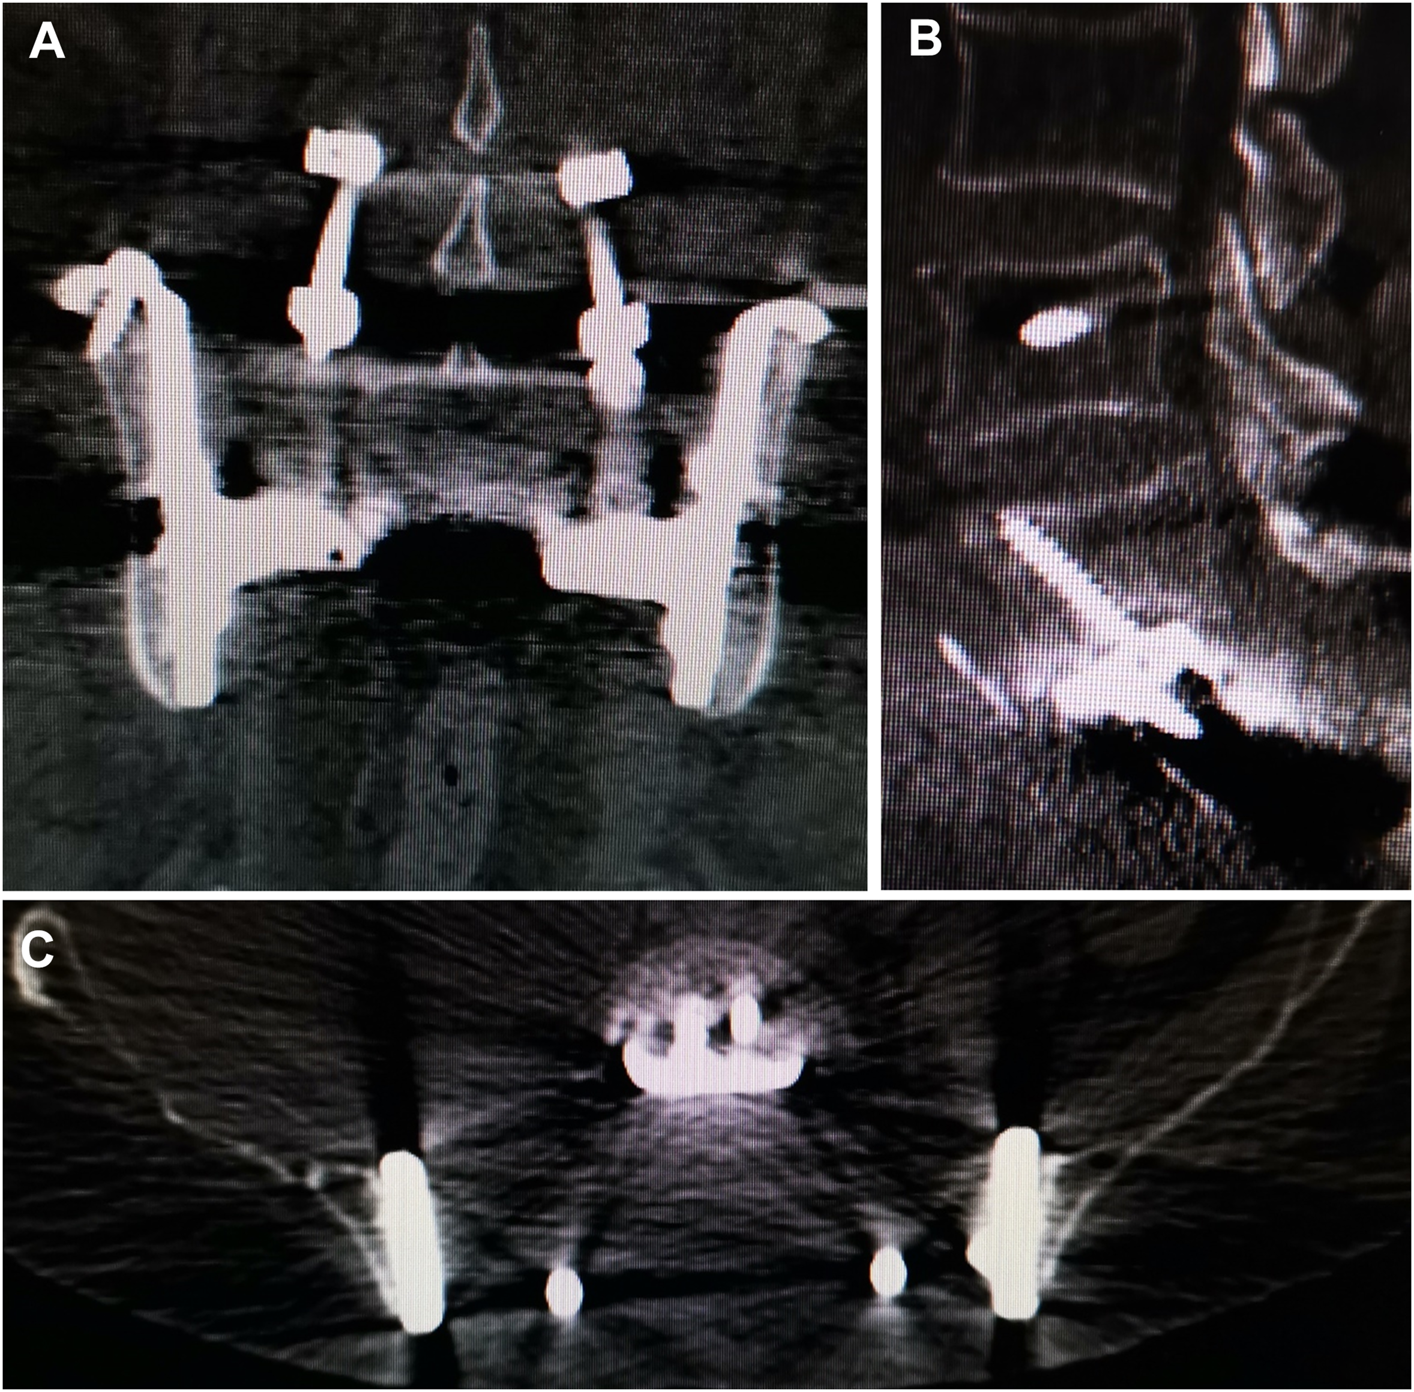

3.5 Implant status

No aseptic loosening and fracture were identied. Osseointegration at the all bone-implant interface was radiographically confirmed in all patients using CT (Figure 5).

FIGURE 5

www.frontiersin.org

FIGURE 5. CT showed excellent osseointegration at the bone–implant junctions in coronal (A), sagittal (B). And axial (C) views.